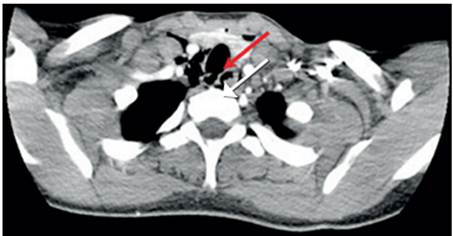

Ante la sospecha clínica de lesión vascular cervical como primera posibilidad, se tomó una radiografía de tórax postero-lateral que descartó la presencia de neumotórax, hemotórax u otra complicación (figura 3). Se realizó un angiotac cervical con contraste endovenoso, encontrando enfisema subcutáneo en los tejidos blandos, con solución de continuidad (figura 4) y una lesión en el tercio medio de la tráquea, con compromiso de su pared lateral derecha (figura 5), sin poder descartar una lesión del esófago en su segmento cervical. No se observó compromiso vascular ni óseo.